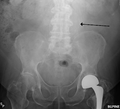

An abdominal aortic aneurysm is usually diagnosed by physical exam, ultrasound, or CT. Plain abdominal radiographs may show the outline of an aneurysm when its walls are calcified. However, this is the case in less than half of all aneurysms. Ultrasonography is used to screen for aneurysms and to determine the size of any present. Additionally, free peritoneal fluid can be detected. It is noninvasive and sensitive, but the presence of bowel gas or obesity may limit its usefulness. CT scan has a nearly 100% sensitivity for aneurysm and is also useful in preoperative planning, detailing the anatomy and possibility for endovascular repair. In the case of suspected rupture, it can also reliably detect retroperitoneal fluid. Alternative less often used methods for visualization of the aneurysm include MRI and angiography.

The faint outline of the calcified wall of an AAA as seen on plain X-ray